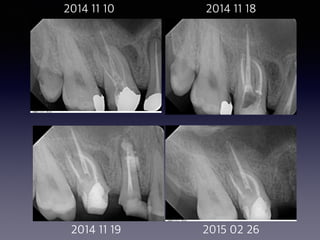

2014 11 10 2014 11 18

2014 11 19 2015 02 26